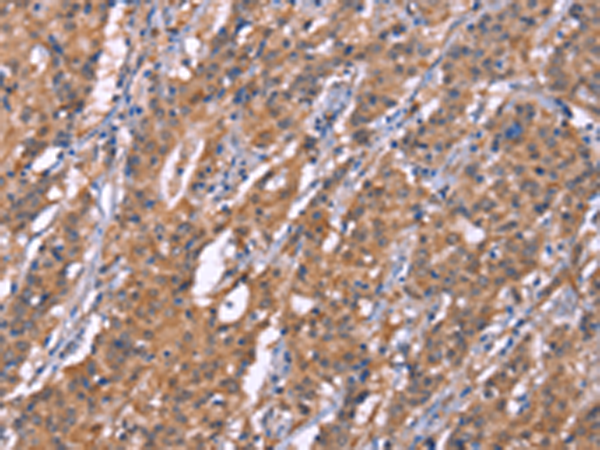

分类: 科研抗体货号: P04893别名:应用: WB,IHC反应种属: Human, Mouse